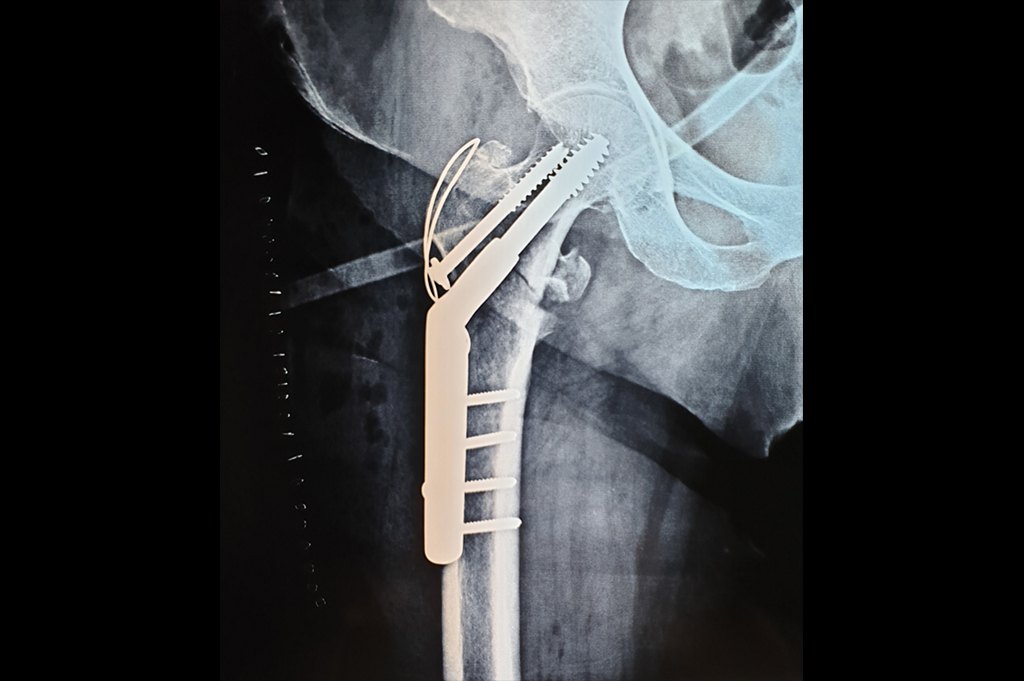

Intertrochanteric Fracture

Neck Femur Fracture